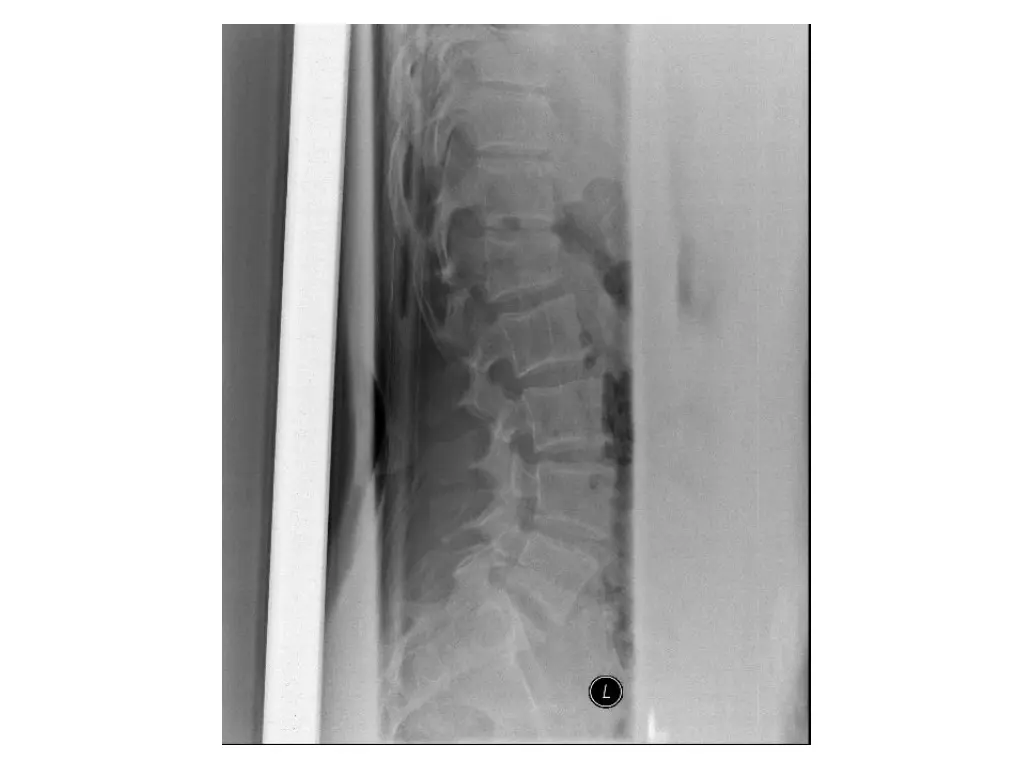

Clinical Hx (Case 2) 30 year old male. Fell approximately 30 feet landing on back. Immediate complaints of back pain. Transported to FMC. Hemodynamically stable. No LoC. Isolated injury to thoracic or lumbar spine.

Neurological exam (Case 2) Upper extremity: Sensory: Normal to light touch and pinprick Motor: 5/5 power in all muscle groups Lower extremity: Sensory: L3-S2 left sided numbness, otherwise normal to light touch and pinprick Motor: 5/5 power in all muscle groups Rectal: Sensation: Normal to light touch and pinprick Voluntary sphincter tone: Normal Other relevant findings: None

Imaging (Case 2) Lateral XR Midsagittal CT scan Parasagittal CT scan Axial CT scan